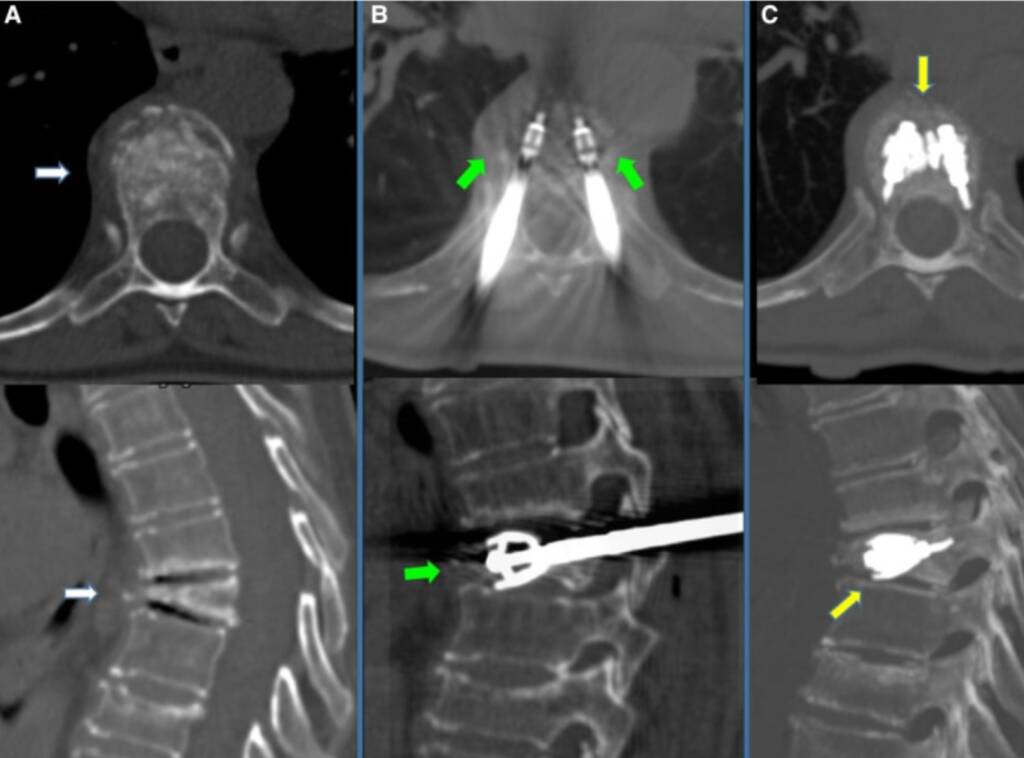

Vertebral compression fractures with significant collapse

Pathological fractures due to metastases or myeloma

Failure or suboptimal response to vertebroplasty / kyphoplasty

In oncologic patients, vertebral implants are often used in combination with cementoplasty and tumor ablation to:

Reinforce structurally compromised vertebrae

Improve biomechanical stability

- Reduce the risk of further collapse

- Optimize local disease management

They are particularly useful in more advanced or structurally complex lesions.